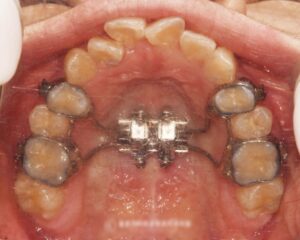

어금니가 어긋난 가위교합(sissors bite) 방치하면 턱관절에도 영향을?! 면목동 교정치과

『반갑습니다, 면목동 글로리 교정치과 김정은 원장입니다.』 오늘 소개해 드릴 케이스는 하나의 문제가 아닌, 여러 문제들을 복합적으로 갖고 있었던 환자의 스토리인데요. ​ 치료를 시작해야 될지 고민이 참 많으셨던 분입니다. 과연 어떤…